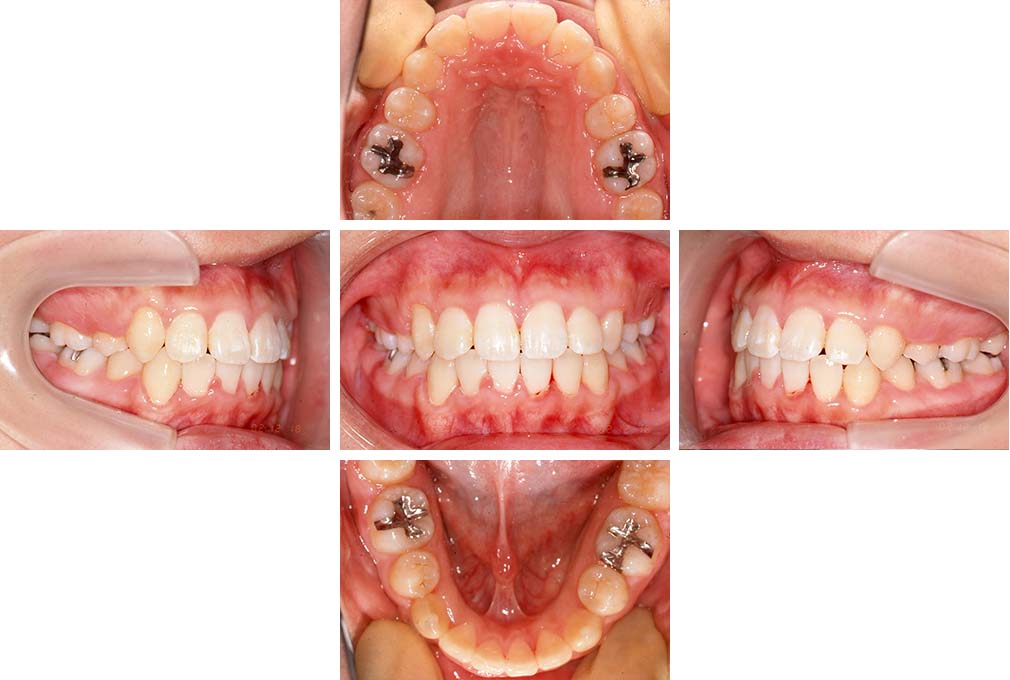

下顎前歯部叢生、小臼歯4歯先天欠損

初診時年齢 14歳3か月

性別 女性

治療費の目安 70万円(治療開始時)

上顎左右側小臼歯3歯、下顎左側第二小臼歯の先天欠損と下顎前歯の叢生を主訴として近隣一般歯科から紹介来院した。

上顎左側第一、第二小臼歯、右側第一小臼歯、下顎左側第二小臼歯が先天欠損であったが、左上第二乳臼歯の根の吸収がほぼ無いことから、これを残すこととして、下顎左側乳臼歯と、右側第二小臼歯を抜歯していただきマルチブラケット装置を使用して動的治療を行った。矯正用ゴムなどの協力状態も良く2年0カ月(調整来院19回)で装置を撤去し保定へ移行した。動的治療終了13年2カ月での来院時には下顎左右側智歯が萌出していたが、垂直的に萌出していたため抜歯は行っていない。

治療前

14歳3か月

治療後

動的治療期間2年0カ月

16歳7か月

13年経過

動的治療終了後13年2カ月

30歳0か月